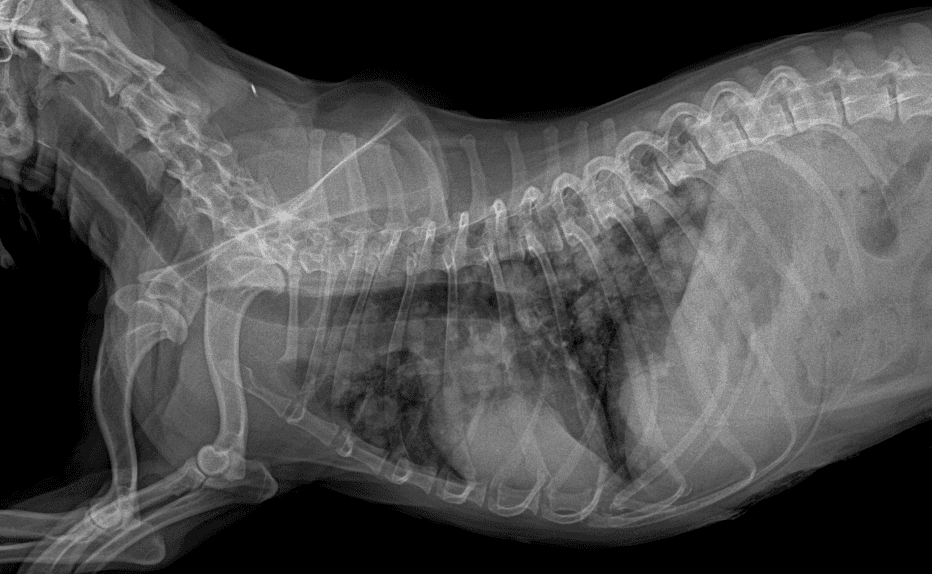

동탄 1 신도시 최초 Aquilion CX/128 slice CT를 동물병원에 도입하였습니다. 최고 사양 CT 모델 Aquilion CX/128 slice를 활용하여 0.5 mm의 얇은 128개의 단면 영상을 신속히 획득 할 수 있어 마취 시간을 단축시킬 수 있습니다. 또한, 128 슬라이스의 고화질의 CT 영상을 통해 영상 왜곡을 최소화하고 X-ray에서는 확인하기 힘든 5 mm 이하의 미세 병변도 확인이 가능하여 정확한 진단을 할 수 있습니다. 심화 진단이 필요한 경우, 조영제 인젝터를 통한 동맥기 촬영으로 종양 유래 확인, 간 질환 진단, 심혈관계 진단이 용이합니다. 저희 동탄시티동물의료센터에서는 본원 환자뿐 아니라 1차 동물 병원과의 CT 촬영 의뢰 시스템을 통해서 원활한 협진이 가능하도록 최선을 다하고 있습니다.

0164 채널 CT 촬영을 통해서 신속하게 고화질 영상을 얻어, 종양 유래 확인 및 전이 평가, 간문맥단락증(PSS), 선천적 뼈 기형과 같은 심화된 진단을 할 수 있습니다.